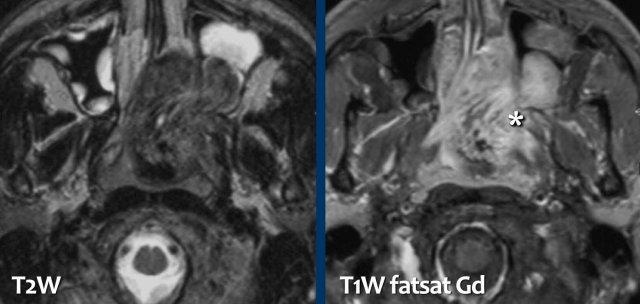

U xơ mạch máu vị thành niên (Juvenile angiofibroma)

Hãy quan sát các hình ảnh trước.

Tại sao đây là hình ảnh điển hình của u xơ mạch máu vị thành niên?

Các dấu hiệu:

- Khối u nằm ở phía sau hốc mũi và tâm tổn thương ở vị trí tương ứng với lỗ bướm khẩu cái (dấu hoa thị).

- Có ngấm thuốc mạnh với hình ảnh “muối và tiêu” (salt and pepper) nhẹ.

Tiếp tục xem hình ảnh DSA…

Hình ảnh DSA cho thấy tình trạng tăng sinh mạch máu, điều này (kết hợp với vị trí đặc trưng) gợi ý mạnh mẽ cho chẩn đoán u xơ mạch máu vị thành niên.

Bệnh nhân này được điều trị tắc mạch (embolization) trước phẫu thuật.

Phẫu thuật cần được thực hiện triệt để nhất có thể để ngăn ngừa tái phát.

Các dấu hiệu là gì?

- Khối u có tâm ở hố bướm khẩu cái bên phải.

- Có giãn rộng hố chân bướm khẩu cái, nhưng không có phá hủy xương.

- Ngay cả trên CT cũng có thể thấy ngấm thuốc rõ rệt.

Đây là hình ảnh điển hình của u xơ mạch máu vị thành niên.

Tiếp tục xem hình ảnh MRI và DSA…

Và một lần nữa các dấu hiệu điển hình trên MRI và DSA.

Có ngấm thuốc mạnh và tăng sinh mạch máu rõ rệt.